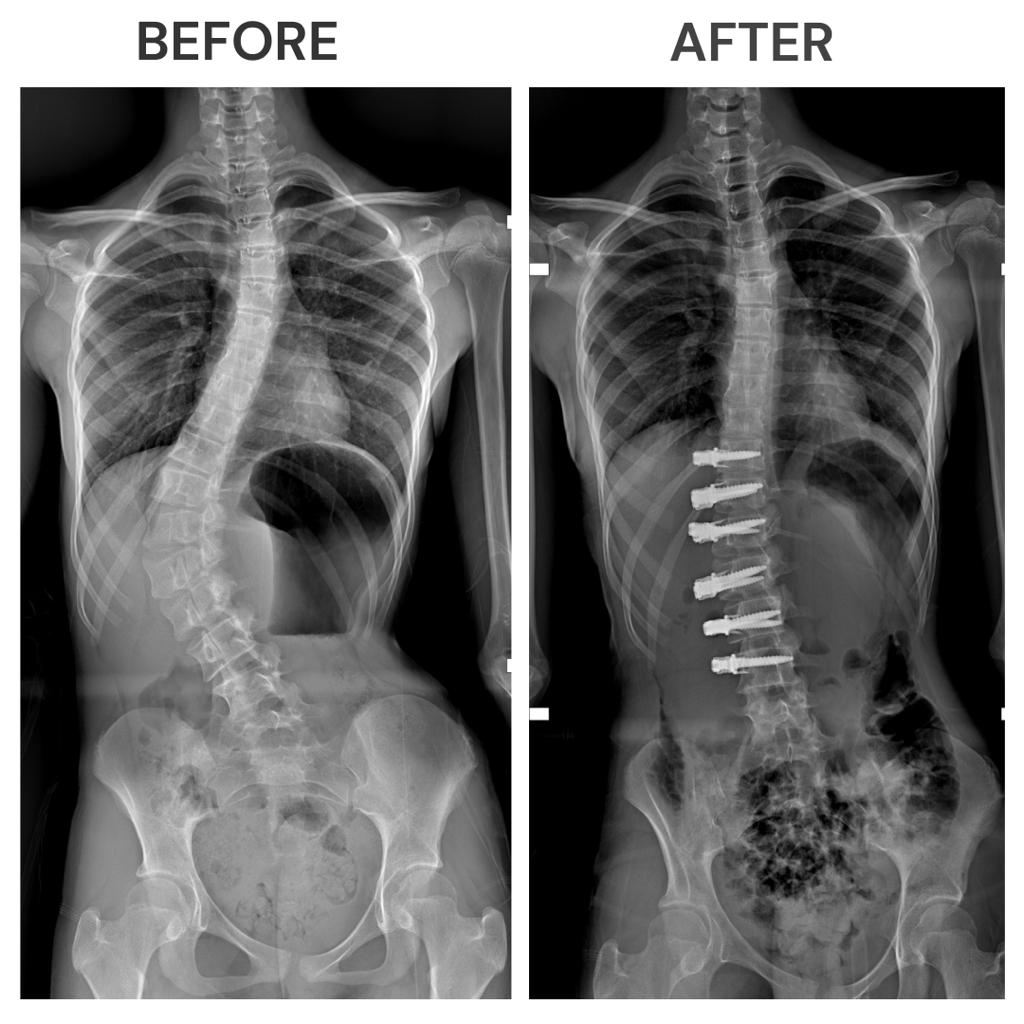

وبعد استشارة العديد من الأطباء في الإمارات ، تواصل والدا سلمى مع الدكتور فراس حسبان، استشاري جراحة العظام في مستشفى برجيل للتوصل إلى حلٍ دائم بشأن حالتها، ووفقًا للدكتور حسبان، عندما جاءت سلمى، وهي طالبة في الصف الثالث المتوسط، كان لديها منحنى صدري قطني بمقدار 65 درجة، وبسبب حالتها، عانت سلمى من تشوه في الظهر مع قصر في الجذع وظهر أحدب سفلي وحوض غير مستوي مع وجود آلام في منطقة الظهر.

قال الدكتور حسبان "أظهر انحناء العمود الفقري لسلمى تحسنًا ملحوظًا، وسيستمر الانحناء في التحسن وسيوجّه الرباط نمو العمود الفقري مع نمو الجسم".